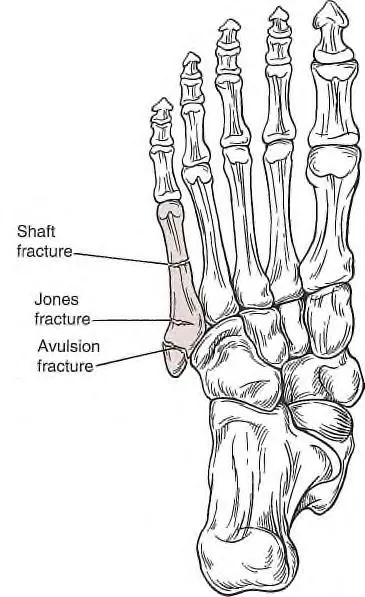

D1. 5th Metatarsal injuries

(1) Pseudo-Jones fracture (Avulsion fx.)

4th, 5th metatarsal base 사이의 articulation의 근위부의 tuberosity에 발생하는 Avulsion fx.

치료는 walking cast와 통증 조절 및 가능하면 체중 부하를 시도한다

(2) Jones fracture

Metaphyseal-diaphyseal junction fracture

불유합 및 지연성 유합의 빈도가 높아 6 ~8주 체중부하금지 Cast 필요, 수술 치료 고려

(3) Shaft fracture (Diaphyseal stress fractures)